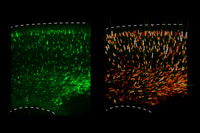

Con el objetivo de entregar soluciones a este complejo problema, el Instituto Milenio de Neurociencia Biomédica (BNI) -que nació de la asociación de investigadores de la Facultad de Medicina de la U. de Chile- plantea un enfoque actual y una estrategia interdisciplinaria integrada.

"La neurociencia no le pertenece a ninguna disciplina", enfatizó Couve, quien explicó que no se puede estudiar neurociencia y sus aplicaciones exclusivamente desde el punto de vista de la biología. Por ende, este es un proyecto de investigación asociativo que ya está funcionando -y con este financiamiento se potenciará- donde convergen las disciplinas de la biología, de la neurobiología, la matemática aplicada, la clínica, la farmacología. "Uno de nuestros principios rectores es que es un ambiente multidisciplinario, y ahí tenemos una ventaja significativa con respecto a otros centros a nivel nacional e internacional", expresó el académico.

Entre los miembros del Centro hay biólogos, bioquímicos, médicos, físicos y estudiantes de diversas disciplinas. La Facultad de Ciencias Físicas y Matemáticas, por ejemplo, se hace presente en él a través del Centro de Modelamiento Matemático, que estudia -a través de las estadísticas- aumentar las probabilidades de detener el proceso degenerativo del cerebro. Este equipo es liderado por el Prof. Jaime Ortega.